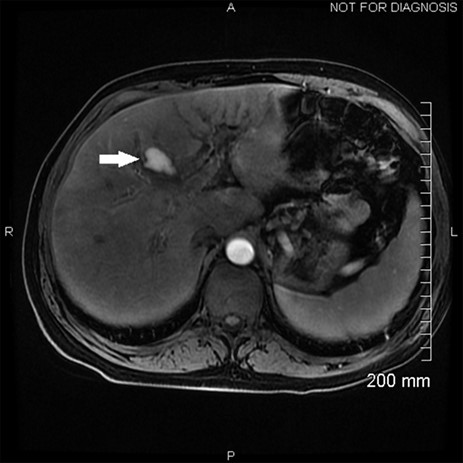

Hemobilia, as seen on this patient’s ERCP, can result from a variety of pathologies though is usually a result of instrumentation of the biliary tract and injury to a nearby vessel [2]. In this case, a hepatic artery pseudoaneurysm formed during his severe cholecystitis, as seen on his MRCP at presentation (Fig. 1). MRI of the abdomen with MRI cholangiogram demonstrated cholelithiasis and pericholecystic edema consistent with cholecystitis. In addition, a 2.6 cm pseudoaneurysm was identified superior to the gallbladder along posterior margins of segment 4A. This is best appreciated on the arterial sampling phase of the liver acquisition with volume acceleration sequence (GE medical systems; Milwaukee, Wisconsin). While pseudoaneurysm due to cholecystitis is rare, the treatment is the same as for any other life-threatening hemorrhage due to arterial fistula to the biliary system, hepatic angiography and transcatheter arterial embolization [2, 3] (Fig. 2). The classic presentation of hemobilia is described by Quinke’s triad: right upper quadrant pain, jaundice and gastrointestinal bleeding, with all three present in only 25–33% of cases [4].